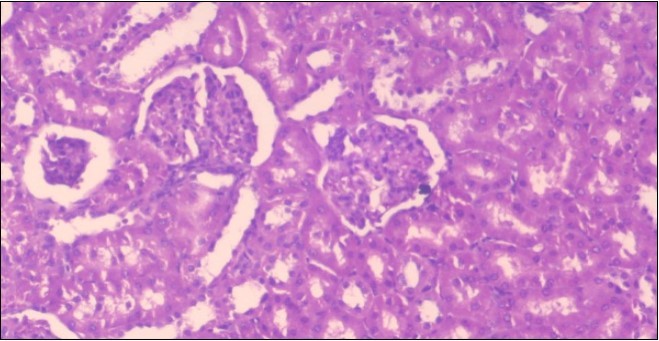

Effect of Ator, Fennel and Their Combination on the Histology of the kidney of the Obese Rats

The histological examination of the kidney of the control rats fed on a standard diet showing normal rounded capsules with normal Bowman's glomeruli, round proximal tubules and elongated distal tubules with high cuboidal cells figure 1. The rats fed (HFD) showed fatty degeneration of the tubules with eosinophilic material deposition, glomerular atrophy with wide urinary space and distal tubules with extrusion of nuclei into lumen figure 2. By comparison kidneys of rats which were treated by fennel after being obese and the control rats observed partial improvement in both Bowman's capsules and proximal tubules. Note the distal tubules show less focal fatty infiltration figure 3.While examination of rats kidney that were treated by ator after obesity showed improvement in Bowman's capsules with normal glomerular and partial improvement in proximal tubules and distal tubules, figure 4. Kidney of rats that were treated by fennel and ator after obesity and the control rats showed high improvement in the tissues with normal glomerular and that Most of Bowman's capsules and renal tubules, restoring their normal appearance figure 5.

Figure 3.Photomicrogragh of kidney section of treated rat with fennel herb showing partial improvement in both Bowman's capsules and proximal tubules. Note the distal tubules show less focal fatty infiltration, (H&E) (40X)

Figure 4.Photomicrogragh of kidney section of treated rat with Ator drug showing improvement in Bowman's capsules with normal glomerular and partial improvement in proximal tubules and distal tubules, (H&E) (40X).